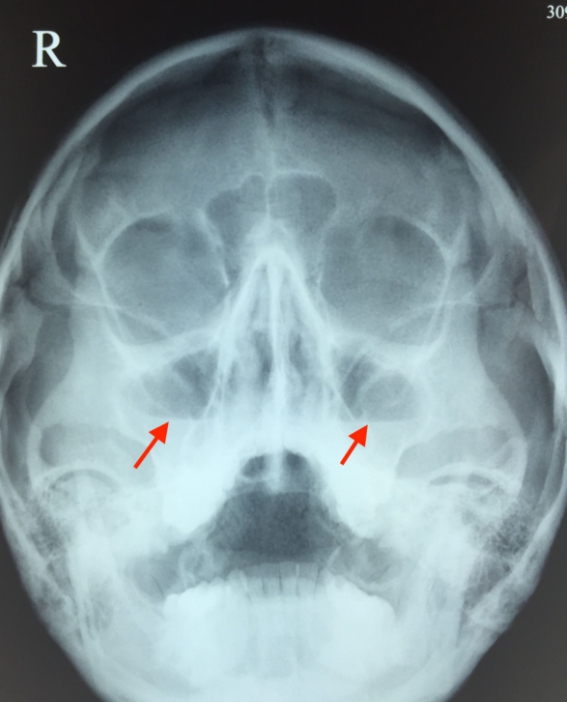

Представленный ниже рентгеновский снимок чётко демонстрирует наличие синусита.

Для определения внешнего вида гайморита на рентгенограмме необходимо осознать, что воспалительные изменения и накопившаяся жидкость проявляются светлыми областями на темном фоне изображения.

При нормальном состоянии придаточные пазухи на рентгеновском снимке не содержат воздуха. На изображении здорового человека они выглядят как темные области по обе стороны от носа и имеют полуовальную форму. Для определения того, является ли область синуса нормальной или патологической, ее оттенок сравнивают с оттенком глазницы. В норме цвет синусов и глазниц совпадает на рентгеновском снимке.

Если воспалительный процесс приводит к заполнению полости жидкостью, которая не может свободно вытекать, то на рентгеновском снимке появляется тень с горизонтальным уровнем.

На этой фотографии отчетливо видно количество жидкости в верхнечелюстных синусах. Медики называют этот рентгеновский эффект «молоко в стакане».

У больного обнаружен гайморит с обеих сторон. Чтобы убедиться в правильности диагноза, проводится рентген в двух проекциях: прямой и боковой. Если на обоих изображениях виден уровень накопившейся жидкости, то диагноз гайморита не подлежит сомнению.

Уже в университетах обучают определять гайморит на рентгеновском снимке (см. фото 5). Здоровые носовые пазухи изображены темными полуовальными образованиями. Гайморит на снимке представлен затемнением в верхних горизонтальных уровнях. По снимку можно отчетливо увидеть тень с волнистым контуром – жидкость такого типа: гнойная, слизистая, катаральная.

Гайморит на рентгене

Почти всегда при гайморите на рентгене (фото 6) обнаруживается характерное изображение, напоминающее молоко в стакане: в черных пазухах видно белое инфильтративное содержимое. Рентгеновский снимок пазух носа при гайморите, в сочетании с диагностическими симптомами, помогает врачу поставить правильный диагноз. Однако при скоплении гноя при гайморите (фото внизу страницы), патологические тени округлой формы не наблюдаются.